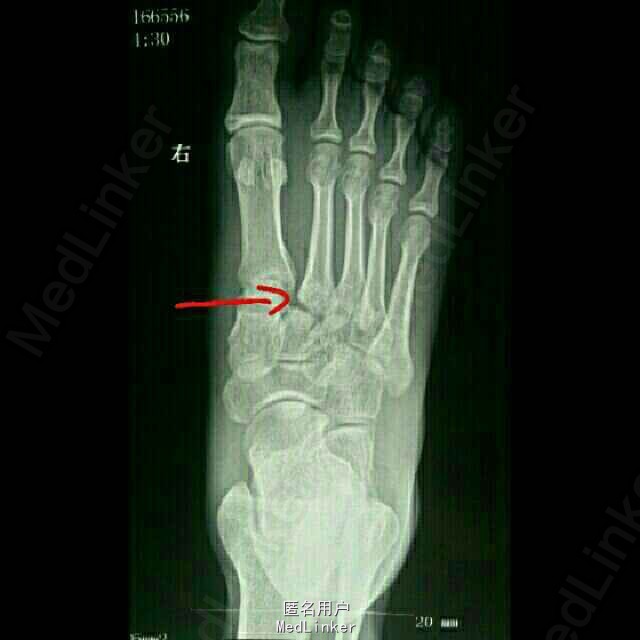

患者青年男性,28岁,负重下楼时扭伤右足1天。右足肿胀痛,活动受限,不能行走。

足背肿胀、青紫,第2—3跖骨基底部压痛阳性,足背动脉搏动弱,各趾未见明显异常。 CT示:右足第2、3跖骨基底部骨折,内侧楔骨、骰骨骨皮质撕脱骨折

诊断:1.右足第2、3跖骨基底部骨折(Lisfranc损失) 2.右足内侧楔骨骨折 3.骰骨骨折 治疗:切开复位内固定